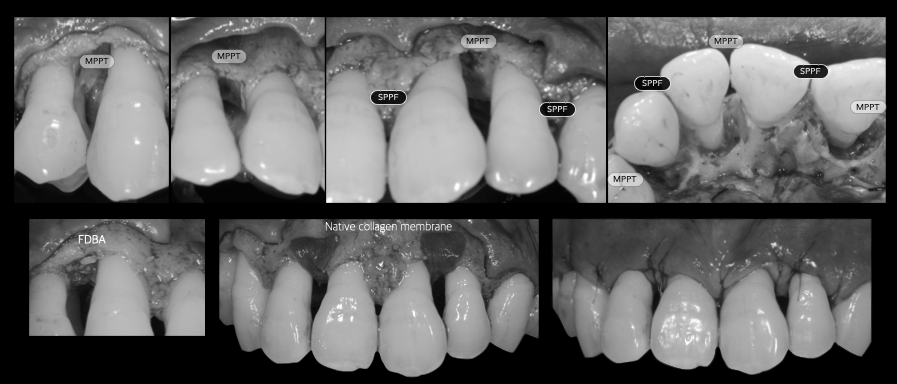

歯周外科、歯周組織再生療法

歯周基本治療では取り切れない場所にある歯石を取るために、歯茎を切開し、目に見える状態で処置をします。また適応であればエムドゲインやリグロスといった再生誘導材料を用いた歯周組織再生療法を行い、失った骨を再生させる治療を行います。

治療例

重度歯周病の症例